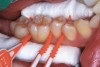

Fig 3. Three thin soft dental picks were used simultaneously for SDF proximal surface saturations in a teenaged patient (Fig 3). After 60 seconds, the treated regions were covered with 5% fluoride varnish (Fig 4). A comparison can be seen of pre-SDF-treatment bitewing films (Fig 5) and 8-month post-SDF bitewing films (Fig 6) for the patient shown in Fig 3 and Fig 4. Radiolucencies were similar or improved, except for contact of maxillary first and second molars.

Figure 3

Interproximal insertion of SDF is demonstrated in different patients in Figure 3 through Figure 11. Various diameters and brands of soft dental picks may be used depending on the closeness of the proximal surfaces and ease of insertion; for example, some picks are designed for use in wider spaces between teeth. This protocol also offers versatility. Figure 3, for example, shows the simultaneous use of three thin soft dental picks to saturate proximal surfaces with SDF in a teenaged patient; the treated regions were subsequently covered with fluoride varnish (Figure 4). This patient was initially treated in April 2019 (Figure 5), with an identical re-application 3 months later. As shown in Figure 6, the December 2019 bitewing film revealed good results with the possible exception of the contact regions of the maxillary first and second molars. New SDF application was completed in the December appointment.